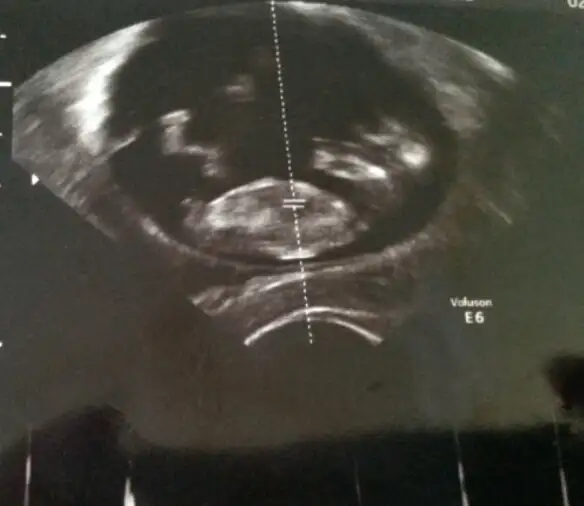

Benim bebiş te cinsiyetini göstermedi daha.tam net değil burda bi tahminde bulunabilir misinz? 12+3 günlüğüz burada

bence erkekBurası aktıflesmıs =) bende tekrar yukleyeyım dedım bebıs burada 11 haftalık teyzelerı siz nub teorısı tahmınlerını yapın bende sıze doktorların tahmınlerını soyleyecegım

bence erkek